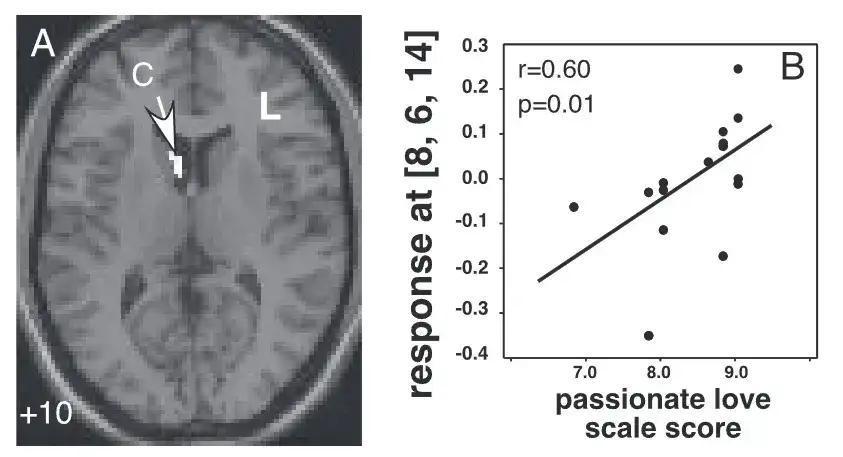

心理学家亚瑟·阿伦(Arthur Aron)等人认为,激情之爱是爱情必不可少的特征之一,尤其是在爱情刚开始的阶段最为明显。他们对此进行了一项脑科学实验,要求 17 名处于热恋期的参与者交替观察爱人和朋友的照片,同时扫描他们的大脑激活状态。结果发现,激情之爱越强烈的人,其动机、奖赏和情绪系统相关的脑区激活也更强,而这正对应了那些所谓“恋爱脑”的表现,包括感性大于理智和强烈想念恋人等。[1]

图源:参考文献[1](注:左图为激情之爱所激活的脑区,右图为激情之爱得分与激活强度之间的相关性。)